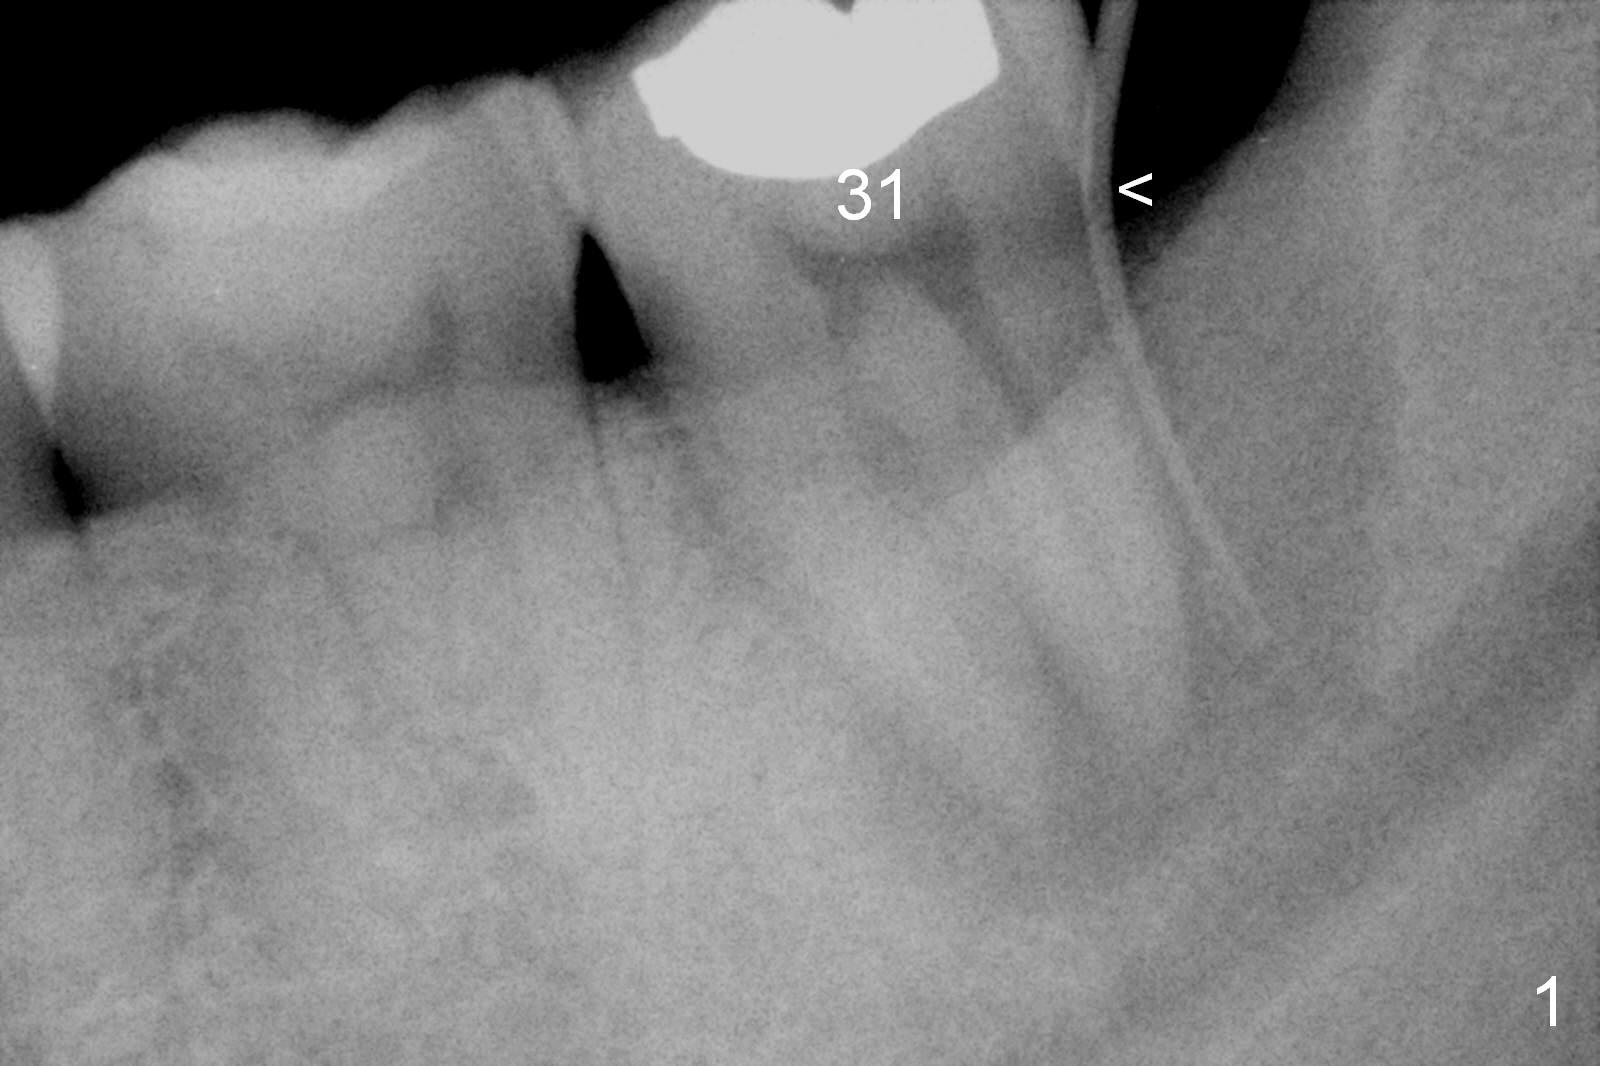

A 55-year-old man must be a dental phobic. With a fistula (Fig.1 <) and large radiolucency associated with the lower left 2nd molar, he postponed root canal therapy for 2 years and 8 months (Fig.2). Later he refused to have crown for the tooth. Three years and 5 months later, the radiolucency seems to have been resolved (Fig.3), but the tooth has fractured with buccal infection. The patient is unwilling to accept treatment of extraction (no antibiotic socket treatment) and immediate implant (Fig.4).